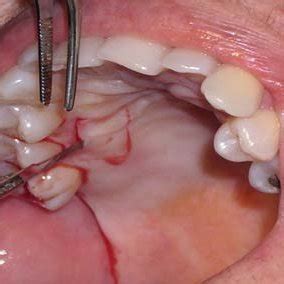

Recubrimiento Radicular (Caso 04)

- Tratamiento de las abrasiones/caries cervicales asociadas a recesiones gingivales.

- Colgajo de reposición coronal con incisiones de descarga.